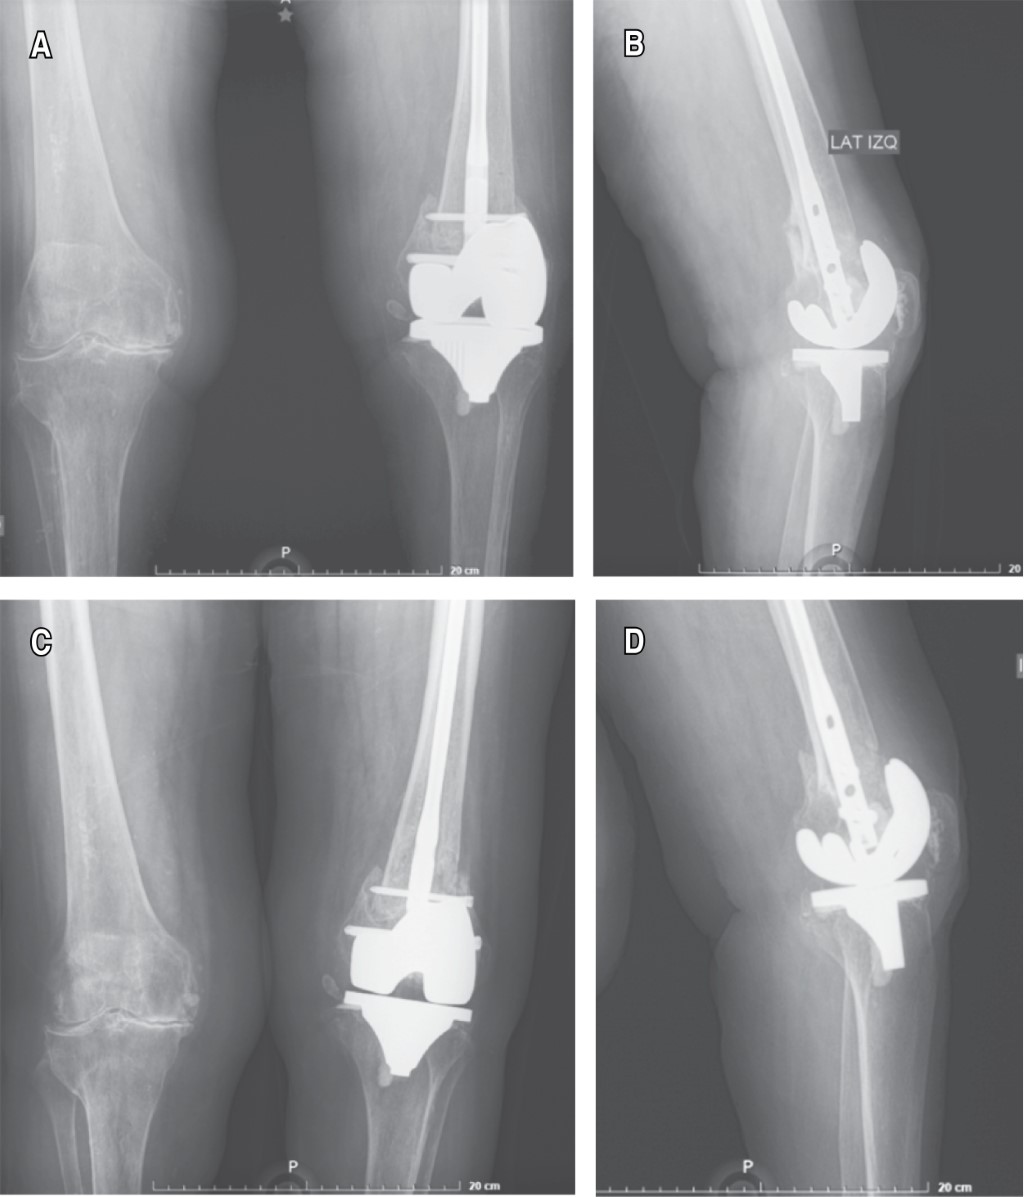

Figure 4